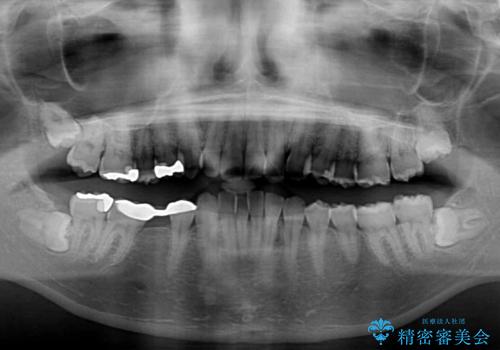

- 上の前歯が下唇に当たる感覚と奥歯の欠損を気にして来院された患者様です。

上顎前歯の突出感は、上顎全体が前方に位置していることが原因であったため、補助装置により上顎全体を後方に移動させることとしました。

後方移動と同時上下歯列をワイヤー装置にて整え、奥歯の欠損部には矯正治療の途中でインプランを埋入していくこととしました。